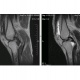

Добрый день, коллеги! Выкладываю материал впервые, поэтому, если что не так, извините. Хотелось бы узнать ваше мнение по поводу костной патологии. Со слов пациента, колено не беспокоило, пока недавно не оступился; в настоящее время ноющая периодическая боль. Заранее благодарю!

По данным снимкам: Кёнига, супрапателлярный бурсит,, внутрикостная ганглиевая киста, инфаркт костного мозга большеберцовой кости. Не люблю единичные снимки. Ещё артроз, проблемы с мениском внутренним.

для Кёнига возраст пациента большенький, как мне кажется. предпочел назвать асептическим некрозом мыщелка. На счет всего остального - есть, без сомнения. За инфаркт - также спасибо, тоже о нем думал (смущает тот факт, что на рентгене пока что без особых изменений). Больше вопросов с кистой. - киста ли? не секвестр как последствие асептического некроза? В минус последнему - форма, не очень похожа. Однако имеется связь с зоной инфаркта.

А есть разница между болезнью Кёнига и асептическим некрозом мыщелка бедра? На рентгене пока рано наверное для обызвествления. Секвестр - не полость, а костный фрагмент в полости, я так по крайней мере понимаю.

На мой взгляд, возможно, условная, но есть. Если понимать буквально (литературные данные), то болезнь Кенига - частичная остеохондропатия, является следствием остеохондральных переломов (при этом собственно травматический анамнез только в 50% случаев), длительной микротравматизации, обычно наблюдается в молодом возрасте. Асептический остеонекроз - дегенеративно-дистрофический процесс, наиболее частым патофизиологическим механизмом которого является хроническая ишемия костного мозга.